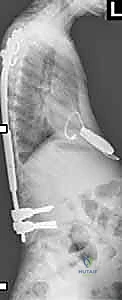

الفكرة العبقرية وراء قضبان النمو هي "التثبيت دون الدمج". يقوم الدكتور هطيف بتثبيت العمود الفقري من الأعلى (عند الفقرات الصدرية العليا) ومن الأسفل (عند الفقرات القطنية أو الحوض) باستخدام مسامير أو خطاطيف تيتانيوم. يتم توصيل هذه المثبتات بقضبان معدنية قوية تمتد عبر منطقة الجنف.

الجزء الأهم: لا يتم دمج (تلحيم) العظام في المنطقة الوسطى المنحنية. هذا يسمح للعمود الفقري بالاستمرار في النمو. مع نمو الطفل، يتم "إطالة" هذه القضبان بشكل دوري لمواكبة زيادة طول الطفل وتصحيح الانحناء تدريجياً.

- تثبيت الدعامات: يتم إدخال مسامير التيتانيوم (Pedicle Screws) أو الخطاطيف بدقة متناهية تحت توجيه الأشعة السينية (Fluoroscopy) في الفقرات العلوية والسفلية.

- إدخال وتشكيل القضبان: يقوم الدكتور هطيف بتشكيل قضبان النمو لتتناسب مع الانحناء الطبيعي المرغوب للظهر، ثم يتم تمريرها تحت العضلات (Submuscular) لتقليل الندبات وتقليل خطر العدوى.

- التصحيح الأولي: يتم ربط القضبان بالمسامير، ويتم إجراء تصحيح أولي آمن للجنف، مع التأكد من إشارات جهاز المراقبة العصبية.

إذا تم استخدام قضبان النمو التقليدية، سيحتاج طفلكم للعودة إلى المستشفى كل 6 أشهر تقريباً.

* كيف تتم الإطالة؟ يتم إجراء شق جراحي صغير جداً (حوالي 2-3 سم) فوق منطقة اتصال القضبان. يقوم الدكتور هطيف بفك القفل، وتمديد القضيب بضعة ملليمترات لمواكبة نمو الطفل، ثم إعادة إغلاقه. تستغرق العملية وقتاً قصيراً جداً، وغالباً ما يغادر الطفل المستشفى في نفس اليوم أو اليوم التالي.